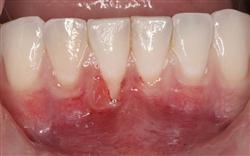

Normally gum tissue surrounds and protects the delicate roots of your teeth. Exposed tooth roots are prone to tooth decay, root canals, discoloration and actual jawbone loss. All of this can lead to tooth loss in advanced cases.

Functional Soft Tissue Grafting replaces the missing gum tissue and protects your teeth. For this reason, soft tissue grafting may be recommended even for back teeth.

In addition to the functional problems previously mentioned, receding gums can look unsightly.

Longer looking teeth and exposed tooth roots give an "old" appearance to your smile. Some people cover their mouths when they smile for this very reason.